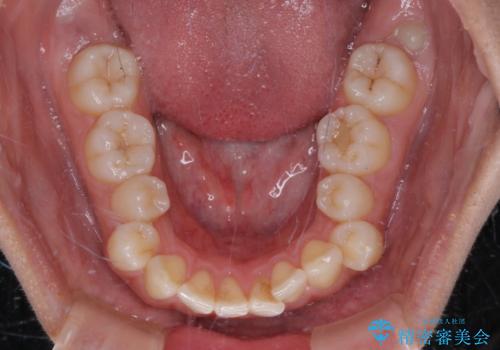

【モニター】突出した前歯 補助装置を併用したインビザライン矯正

- 上下前歯が非接触となり、前方に突出していることを気にして来院された患者様です。

咬合力が強く、全体的に歯がすり減っているため、インビザライン単独での上顎歯列移動は困難と判断し、補助装置により上顎歯列を後方移動させ、その後インビザラインにて仕上げていくこととしました。

補助装置なしでも改善できる可能性はありましたが、補助装置で確実性を上げ、短期間できっちりと仕上げることができました。